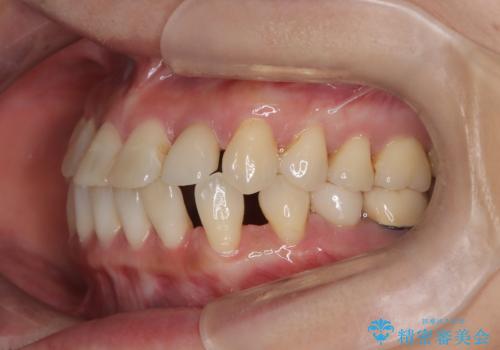

- 歯と歯の間に大きなスペースがある「空隙歯列(すきっ歯)」と、一部の歯が欠損していることによる噛み合わせの不安定さを主訴にご来院されました。

精密検査の結果、全体の隙間を閉じるだけでは適切な咬合バランスが得られないため、まずはインビザラインを用いて歯の位置を理想的な場所へと整える計画を立案しました。矯正によって欠損部位に適切なスペースを確保した後、その部分にインプラントを埋入することで、審美性と機能性の両立を目指しました。